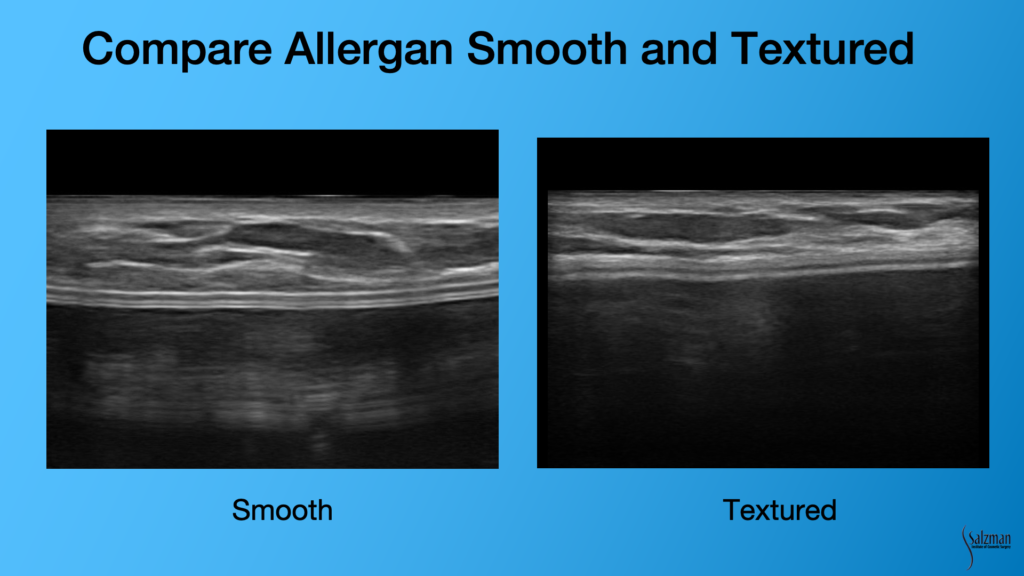

Comparing Smooth vs Textured Implants

You can tell the difference easily between a smooth and textured implant. Sometimes the patients don’t remember which surgeon placed the implant and they can’t tell you if it’s smooth or textured or what brand of implant they had. You can tell with ultrasound. The implant on the left clearly has a more smooth, bilaminar or railroad track sign. The image on the right looks almost out of focus because of the fuzzy surface of a textured implant. Inside the implant, sometimes you’ll see what we call reverberation artifact. They are these white lines that look like the shell. Often, they are almost the whole length of the image, and they repeat one another. And that’s non-pathologic. You’ll see that a lot of the times inside – it won’t be a totally anechoic structure of the gel.